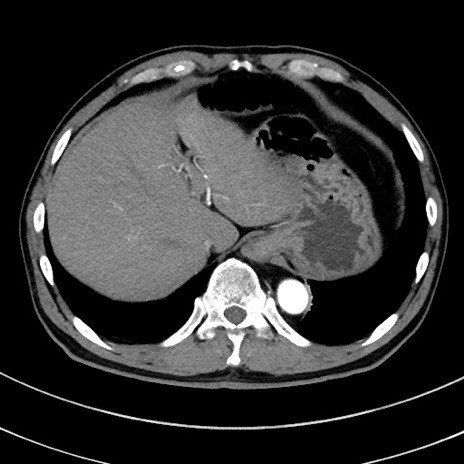

症例8(横断像)

【症例】 60歳代男性

【主訴】 黒色吐物

【現病歴】 4日前から嘔気自覚、2日前の朝食後にも嘔気あり、自分で手で嘔吐反射起こし嘔吐したところ血が混ざっていたため受診。

【既往歴】 5年前汎発性腹膜炎を伴う急性虫垂炎で手術、高血圧、前立腺肥大症、高脂血症

【身体所見】 腹部正中に手術癩痕あり 腹部平坦・軟圧痛なし膨満感あり

【データ】WBC 8400、CRP 4.54